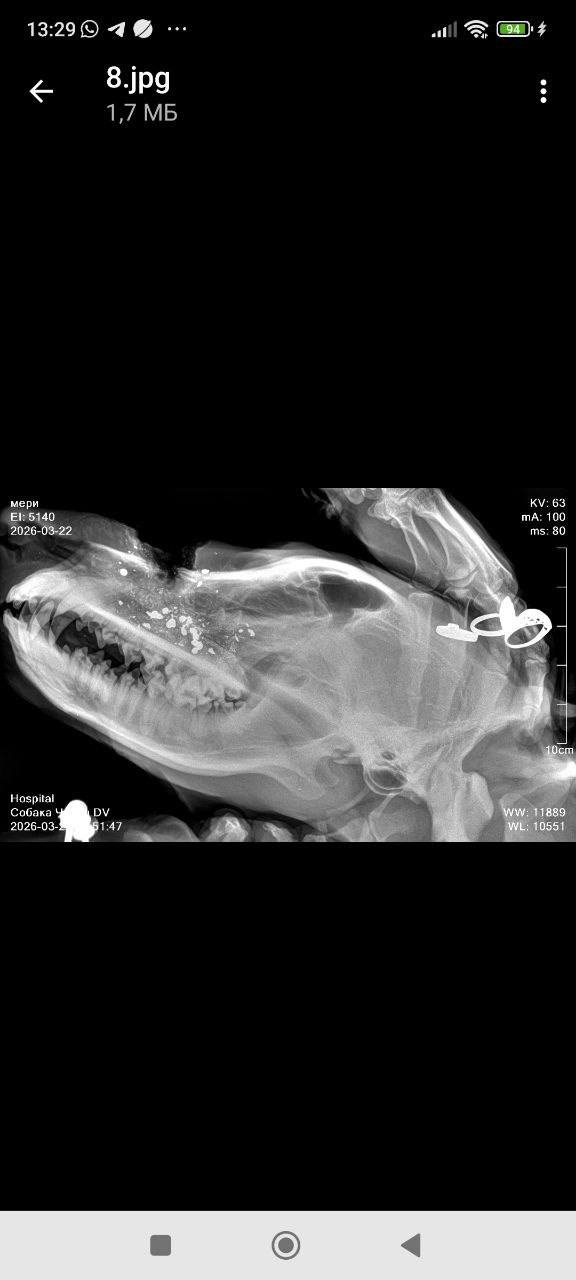

По словам очевидцев, пострадали как минимум четыре животных. Одна собака погибла на месте, две скрылись после ранений. Еще одно животное в тяжелом состоянии доставлено в ветеринарную клинику. Врачи борются за его жизнь.